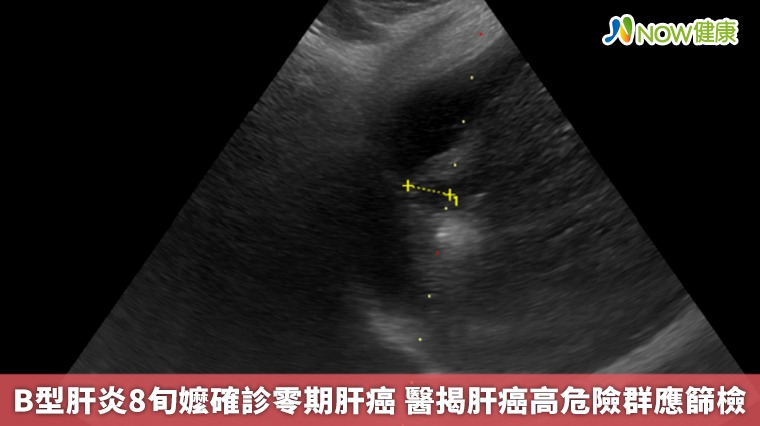

【NOW健康 林郁敏/新北報導】一名83歲的黃姓老婦人因身體不適到台北慈濟醫院就診,就診過程中意外發現肝功能異常,進一步檢查發現一顆約1.5公分的肝臟腫瘤,確診為第零期肝癌,同時也發現患者患有B型肝炎,卻因沒有症狀所以不曾進行相關治療。所幸發現及時,由胃腸肝膽科醫師鄭煜明執行電燒治療,術後三天患者順利出院,目前僅需定期追蹤避免復發。

▲台北慈濟醫院胃腸肝膽科醫師鄭煜明提醒,肝臟疾病通常在初期難以發現,容易錯過治療佳機,建議45歲以上民眾終生主動接受一次B、C型肝炎篩檢。(圖/台北慈濟醫院提供)